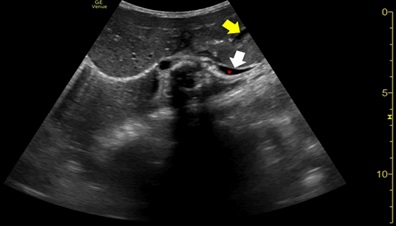

For preoperative evaluation, imaging was repeated on day two of life. Abdominal ultrasound and upper gastrointestinal series (figure 4) revealed the stomach now in anatomic position, intra-abdominal, with regular gastric emptying and significant gastro-oesophageal reflux. Diaphragmatic ultrasound disclosed a reduced thickness of the left hemidiaphragm and a reduced diaphragmatic excursion on this side (figure 5). Given these results, enteral feeding was started on day three and was initially well tolerated.

Figure 5: Diaphragmatic ultrasound on day 2 showing left hemi diaphragmatic reduced thickness and excursion (white arrow). Mild left pleural effusion is also seen (red asterisk). An almost empty intra-abdominal stomach can also be noticed (yellow arrow) in the anatomic position.

However, on day seven, frequent episodes of tachypnoea and desaturation after meals and a 20-mmHg systolic differential between upper and lower limbs were noticed, with poor perfusion. Echocardiogram demonstrated a dynamic left atrium, which was being compressed by the stomach (figures 6 and 7), with repeat diaphragmatic and abdominal ultrasound (figure 8) and thoracoabdominal contrast radiography (figure 9) showing recurrence of the hiatal hernia, prompting cessation of enteral feeds.

Figure 8: Abdominal ultrasound showing large hiatal hernia (arrow).

Figure 9: Abdominal ultrasound showing large hiatal hernia (arrow).